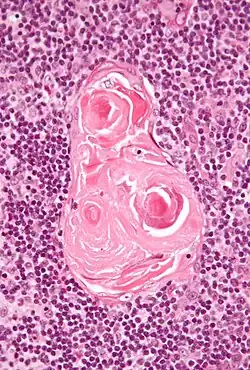

Hassall-Körperchen (lat. Corpuscula thymi) sind runde, schichtweise Zusammenballungen von mehreren Thymusepithelzellen in einem normalen Thymus. Sie sind besonders im Thymusmark anzutreffen. Die Thymusepithelzellen zeigen im Zentrum des Hassall-Körperchens Zeichen der Degeneration und des Zelluntergangs. Sie entstehen während der Embryonalentwicklung aus dem Ektoderm und durchlaufen eine ähnliche Zelldifferenzierung wie Zellen der Epidermis; in ihnen konnte daher Keratin und Präkeratin nachgewiesen werden.[1]

Die Funktion der Hassall-Körperchen ist unklar, und ihre Präsenz und Morphologie ist zwischen verschiedenen Spezies sehr unterschiedlich; in Thymusgewebe von Mäusen sind sie beispielsweise nicht vorhanden. Ihre Anzahl steigt bis zur Pubertät an, um danach mit dem Abbau des Thymus zum Retrosternalen Fettkörper zu verschwinden. Sie können im Inneren verkalken oder zystisch degenerieren. Möglicherweise spielen sie eine Rolle bei der Entfernung apoptotischer Thymozyten oder bei der Reifung von T-Lymphozyten, da sie das Zytokin TSLP (thymic stromal lymphopoietin) enthalten.[2][3]